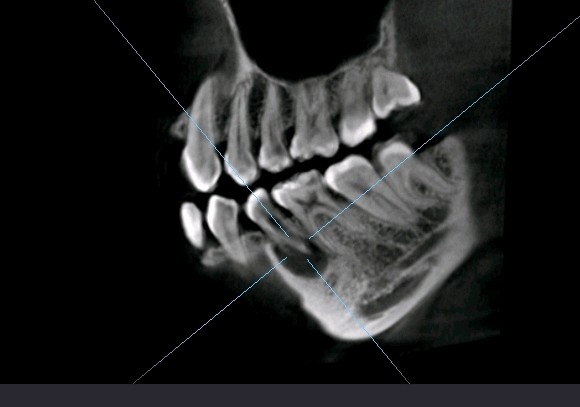

畸形中央尖多发生于下颌第二前磨牙,是一种牙体形态的发育异常,畸形中央尖本身不是什么大问题,只是折断或者磨穿了才会有不好的后果。这位患者就是因为没有长期的磨耗使的根尖周发生炎症时,导致根尖发育停止,根管口呈喇叭口状。对于这种牙根过短,根尖炎症范围过大的患牙,则考虑给予拔除。拔出后植入骨粉骨膜,后期种植修复。

术前